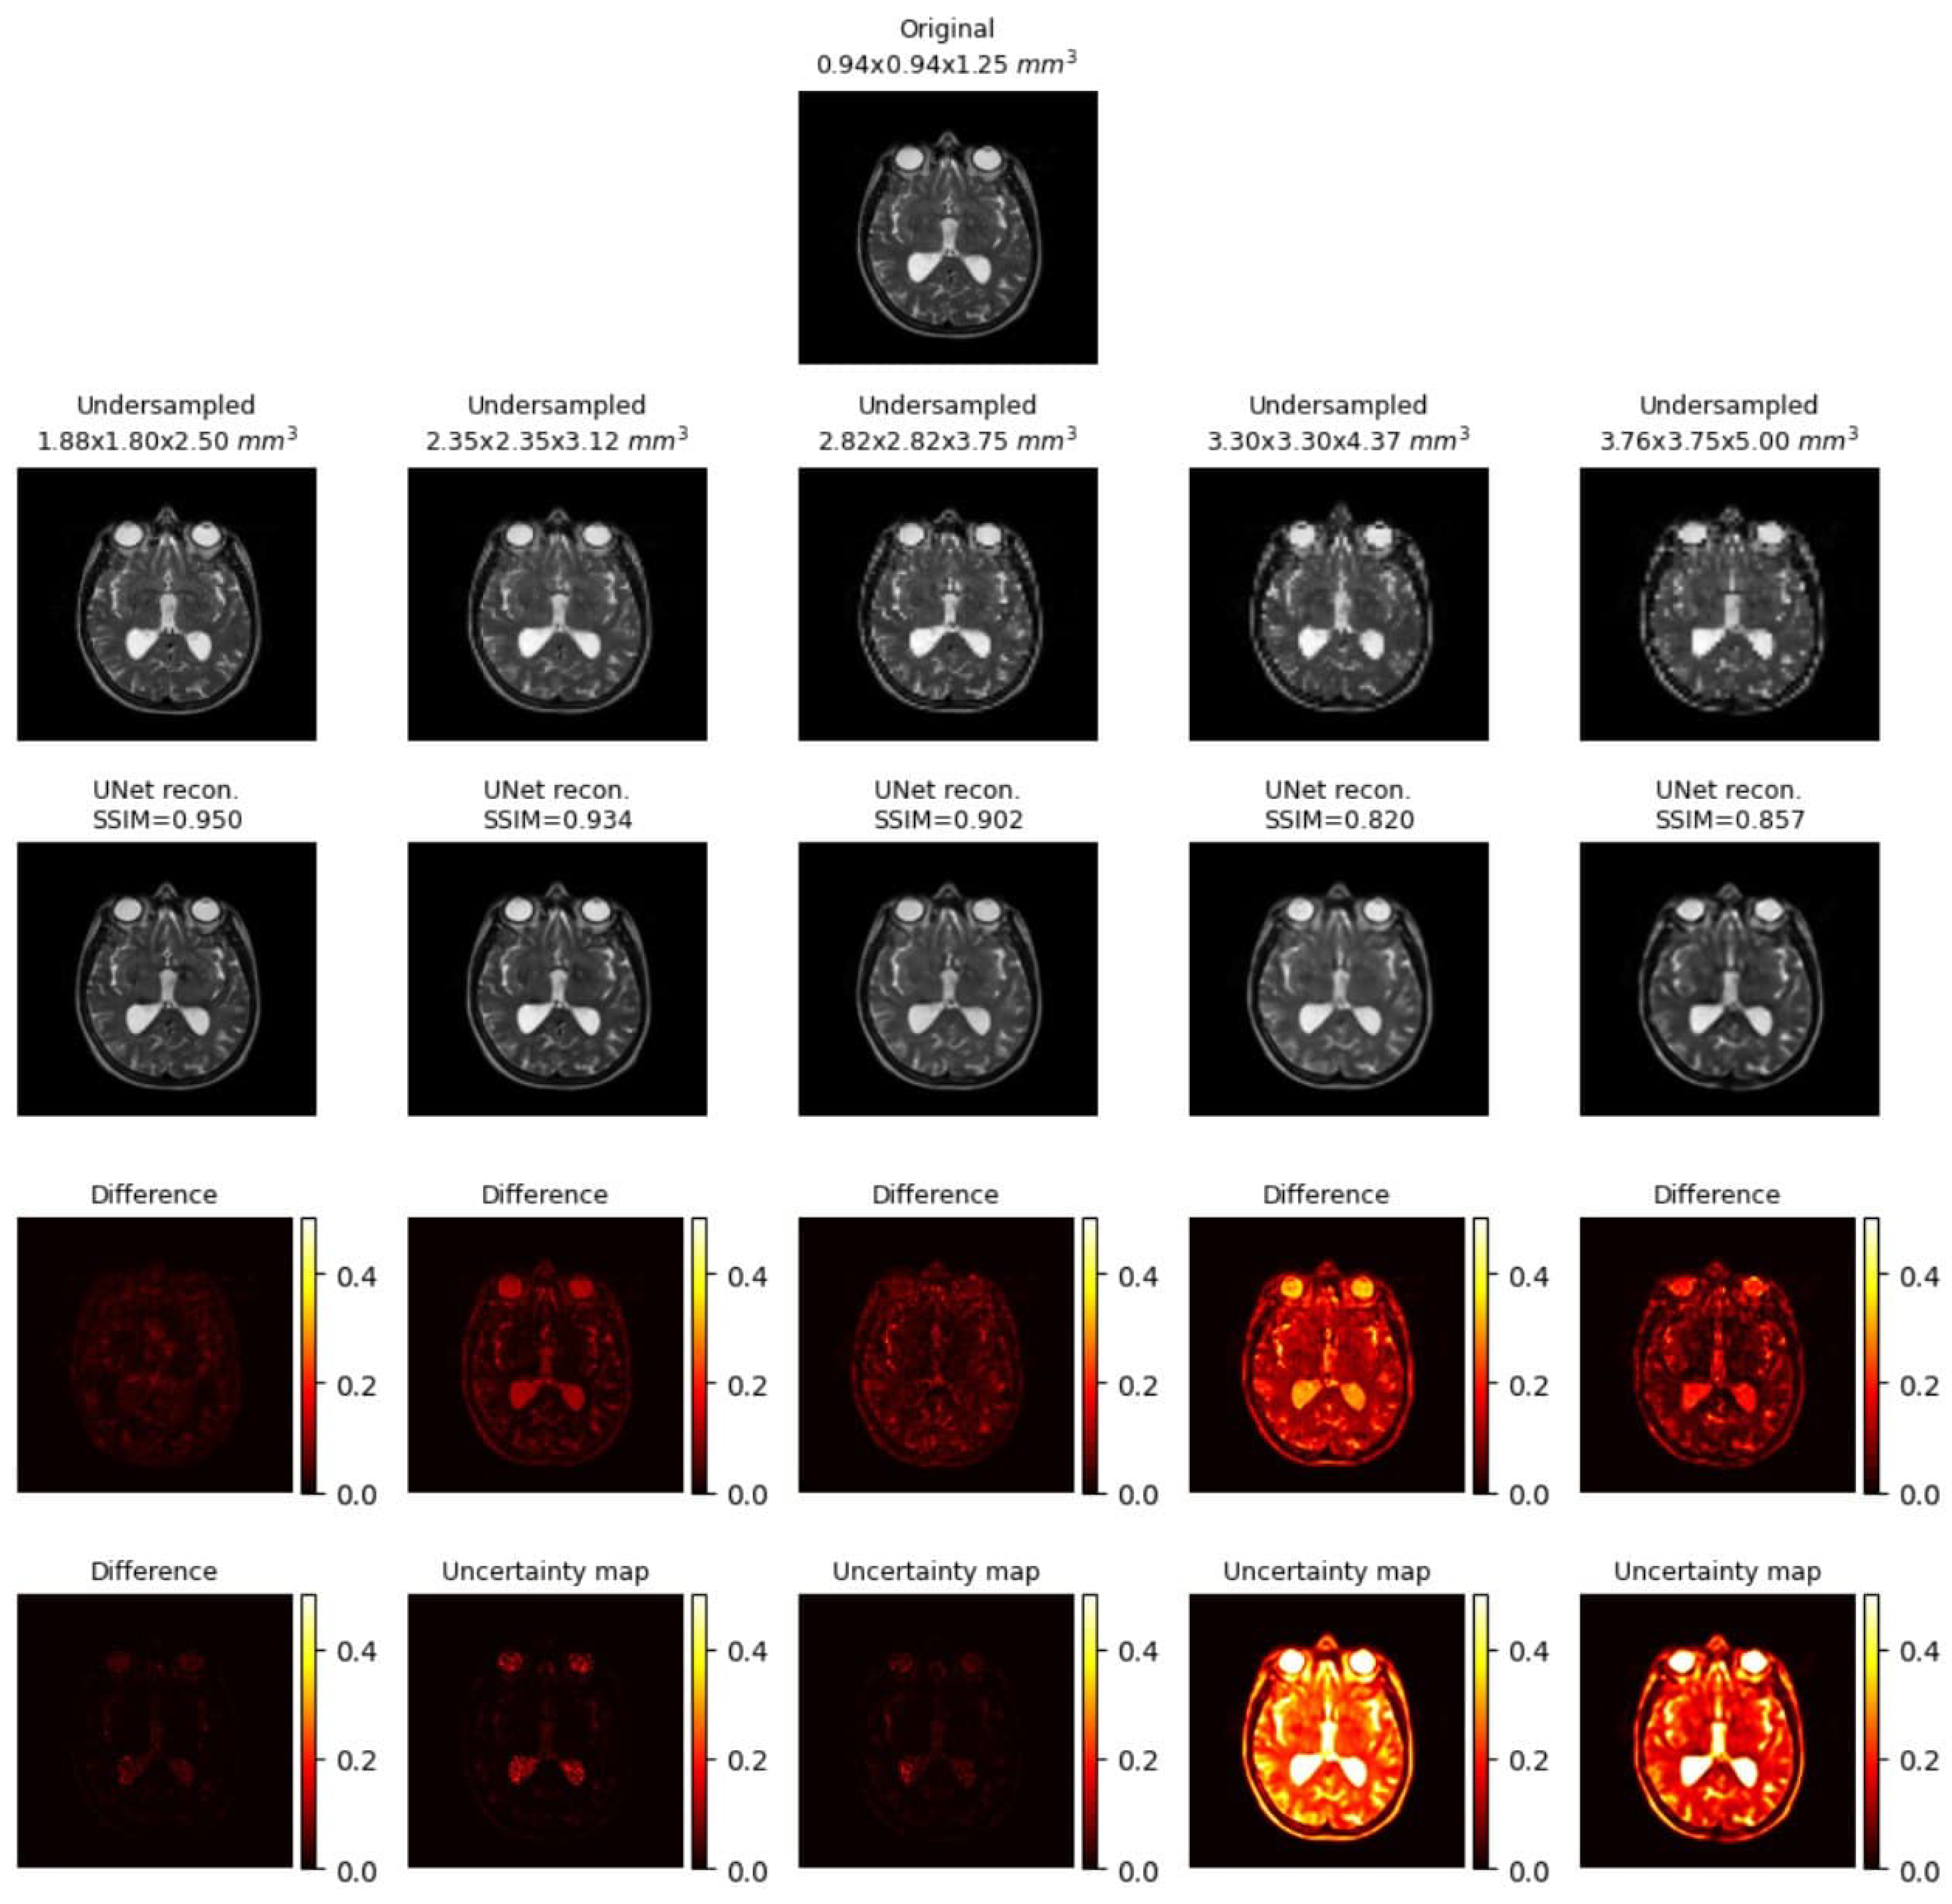

Uncertainty Mapping

2.4. Uncertainty Mapping

Uncertainty Mapping Pipeline

- 1.

- Iteratively, model predictions are generated from low-resolution images using the trained model weight but with different dropout rates and Gaussian noise in the intermediate layers.

- 2.

- Compile all the generated images.

- 3.

- The uncertainty map is the pixel-wise variance across all these generated images.